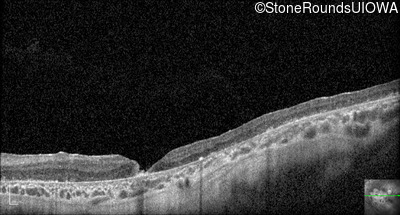

Optical Coherence Tomography - Left - 10/300

Exemplar / OCT Stack

OCT Stack